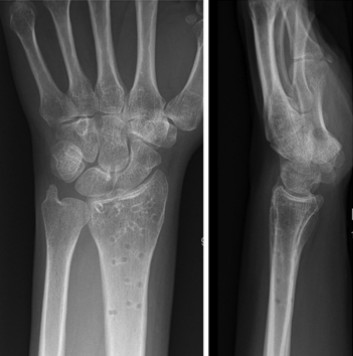

Случай ③